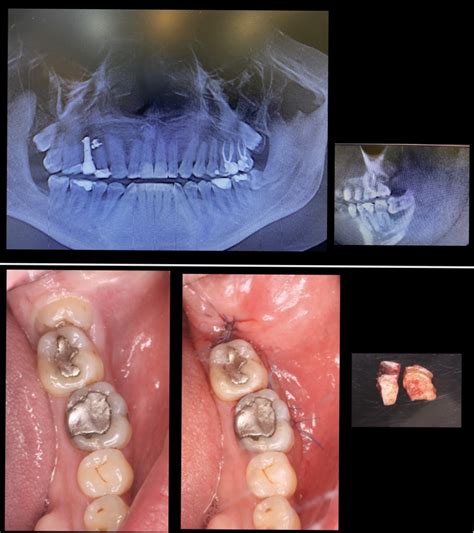

Desplazamiento de Terceros Molares e Instrumentos

El desplazamiento accidental de terceros molares impactados, un fragmento radicular, la corona o todo el diente, no es frecuente durante la extracción, pero de cualquier manera es una complicación conocida que se menciona con frecuencia. Cuando un fragmento radicular «desaparece» durante la extracción, no debe intentarse su recuperación. El paciente debe remitirse de forma inmediata al especialista.

Otra posibilidad de desplazamiento del tercer molar superior es su luxación a la fosa infratemporal. Algunos trabajos describen el desplazamiento del tercer molar a los espacios submandibular, sublingual, pteriomandibular, faríngeo lateral o área cervical lateral. El paciente experimentó inflamación recurrente en el espacio submaxilar derecho. Durante 14 meses, el mismo clínico supervisó el tratamiento con antibióticos. Se encontró una fresa de 20 mm de diamante en el espacio submandibular.